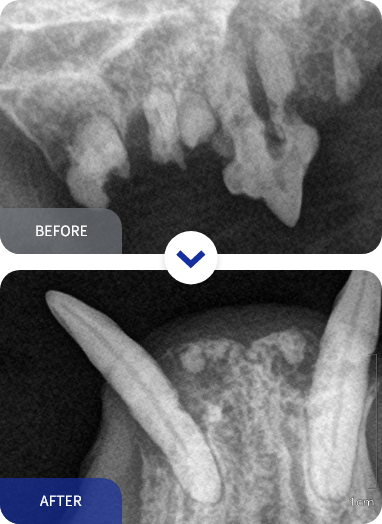

치과 방사선은 촬영은 치과 치료의 시작입니다.

눈으로 보이는 치아의 부분은 치아의 아주 일부분입니다.

치아 뿌리, 치조골의 상태는 치과 방사선만으로 확인이 가능합니다.